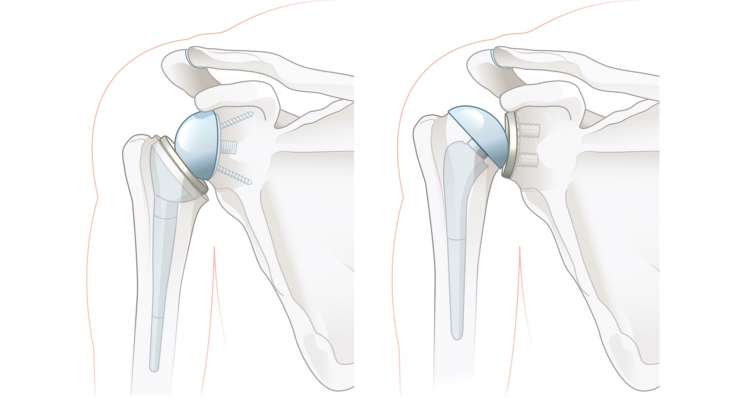

остеоартроз плечевого сустава

Профессор, доктор медицины Франк Мартечшлегер лечит артроз плечевого сустава (оартроз) в зависимости от стадии заболевания с помощью консервативных методов или с использованием современных протезов плечевого сустава, чтобы облегчить боль и восстановить подвижность надолго.